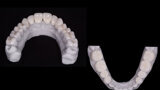

Fig. 10: Final veneers and crowns digitally prepared using the Ceramill Mind design software and produced in a milling machine (Ceramill

Motion 2) from machinable lithium disilicate ceramic blocks (VITABLOCS TriLuxe forte).